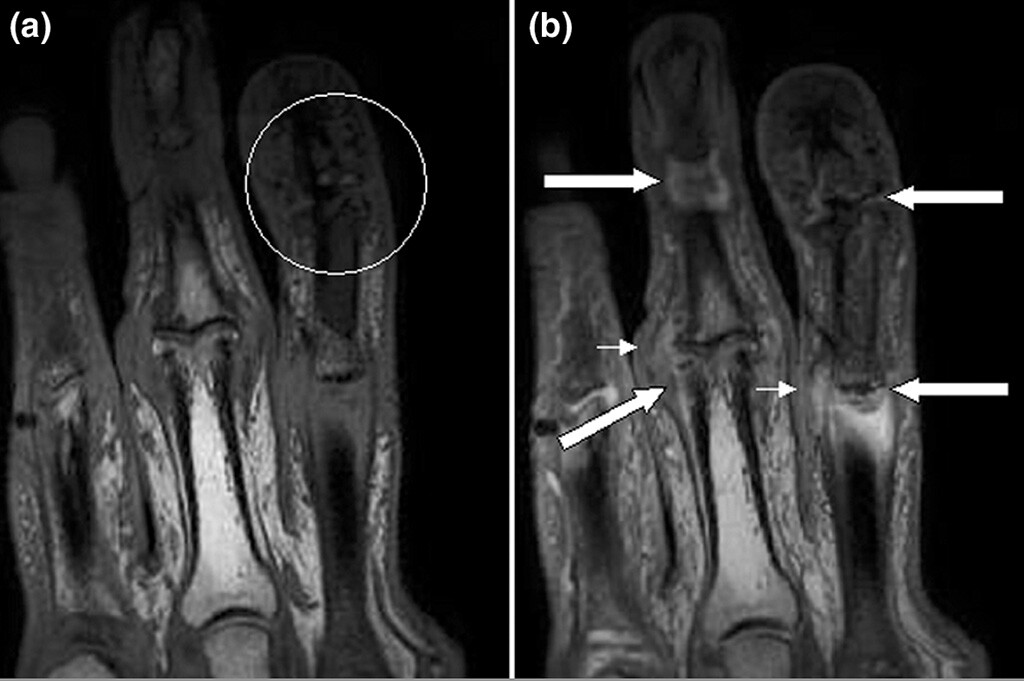

psoriasis arthritis